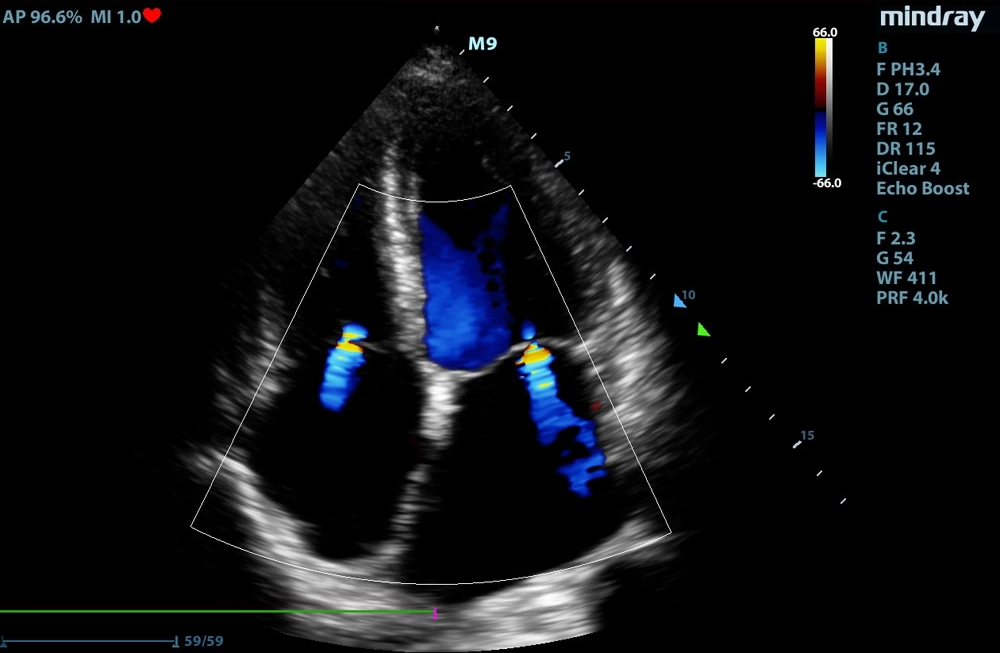

Jak wygląda echo serca zwierzaka

Badanie echo serca wykonywane jest na pacjencie leżącym w pozycji bocznej lub stojącym.

Trwa od kilku do kilkunastu minut, czas ten w dużej mierze zależy od ruchliwości zwierzęcia. Przy mocno podekscytowanych i niespokojnych zwierzętach warto, jeśli to możliwe, przeprowadzić badanie w obecności dwóch opiekunów.

Po zakończeniu badania usg opiekun otrzymuje jego opis wraz ze zdjęciami i zaleceniami co do ewentualnego leczenia.